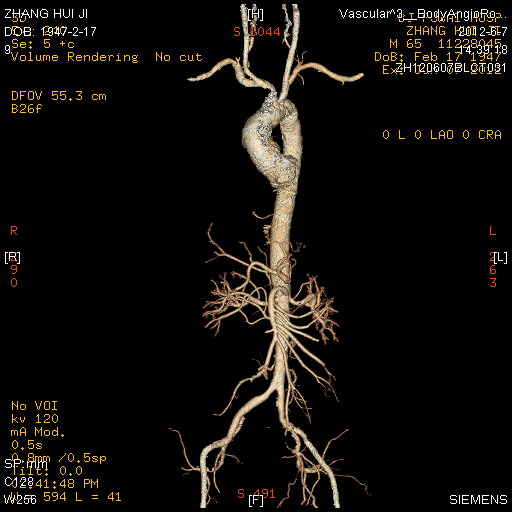

图2:CT三维重构图示钙化主要累及升主动脉、无名动脉和双侧颈动脉